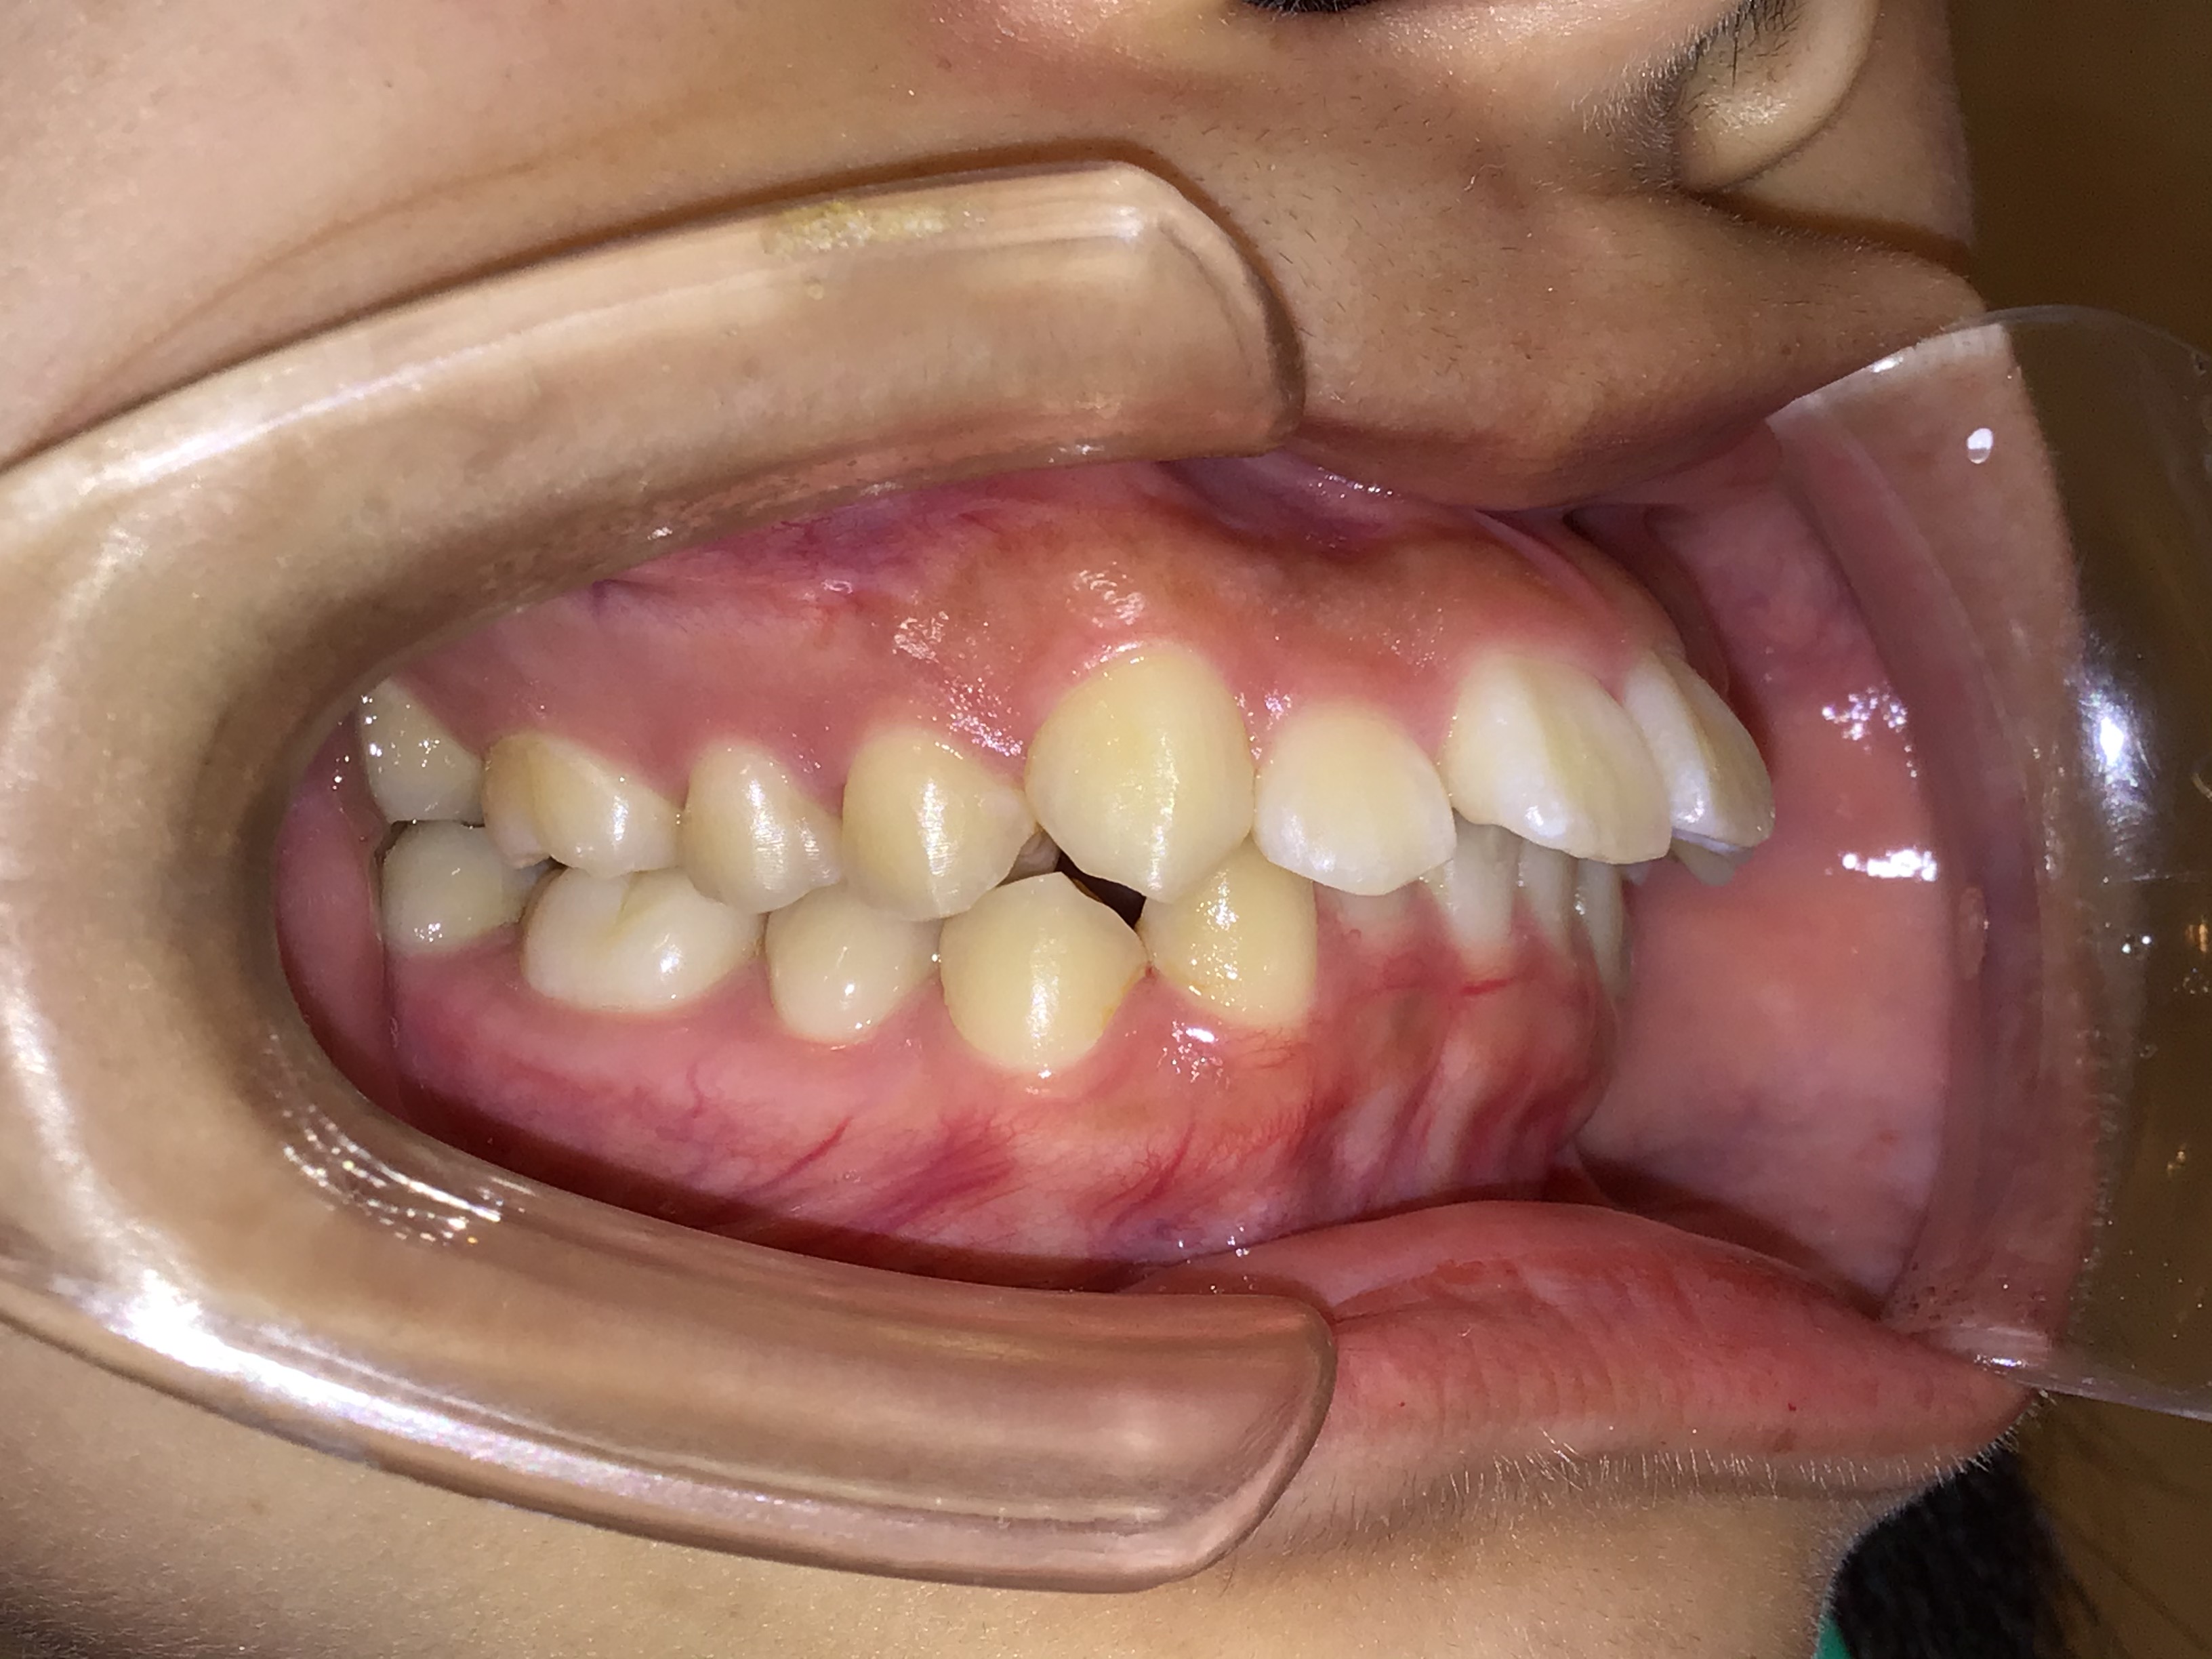

治療前 治療後 | 主訴 | 下の歯が出ている |

| 診断 | 歯槽性下顎前突症 |

| 初診時年齢 | 11歳5ヶ月 |

| 治療種別 | 本格矯正 |

| 外科処置 | 下顎右第二乳臼歯、左第二小臼歯の抜歯 |

| 主な治療装置 | マルチブラケット装置、矯正用アンカースクリューなど |

| 治療期間 | 3年3ヶ月 |

| 治療費 | 90万円(税別) |

| リスク・副作用 | 矯正装置による不快感や痛みが生じることがあります(数日〜1、2週間で慣れることが多いです)。歯の動き方には個人差があり、予想された治療期間が延長する可能性があります。歯を動かすことにより歯根が吸収して短くなることや、歯ぐきがやせて下がることがあります。治療中は装置が付いているため歯が磨きにくくなり、むし歯や歯周病のリスクが高まります。治療途中に金属等のアレルギー症状が出ることがあります。顎関節症状(音が鳴る、あごが痛い、口が開けにくい)が出ることがあります。装置を外す時にエナメル質に微小な亀裂が入る可能性があります。装置が外れた後、保定装置を指示通り使用しないと後戻りが生じる可能性があります。治療後に親知らずが生えて凸凹が生じる可能性があります。 |